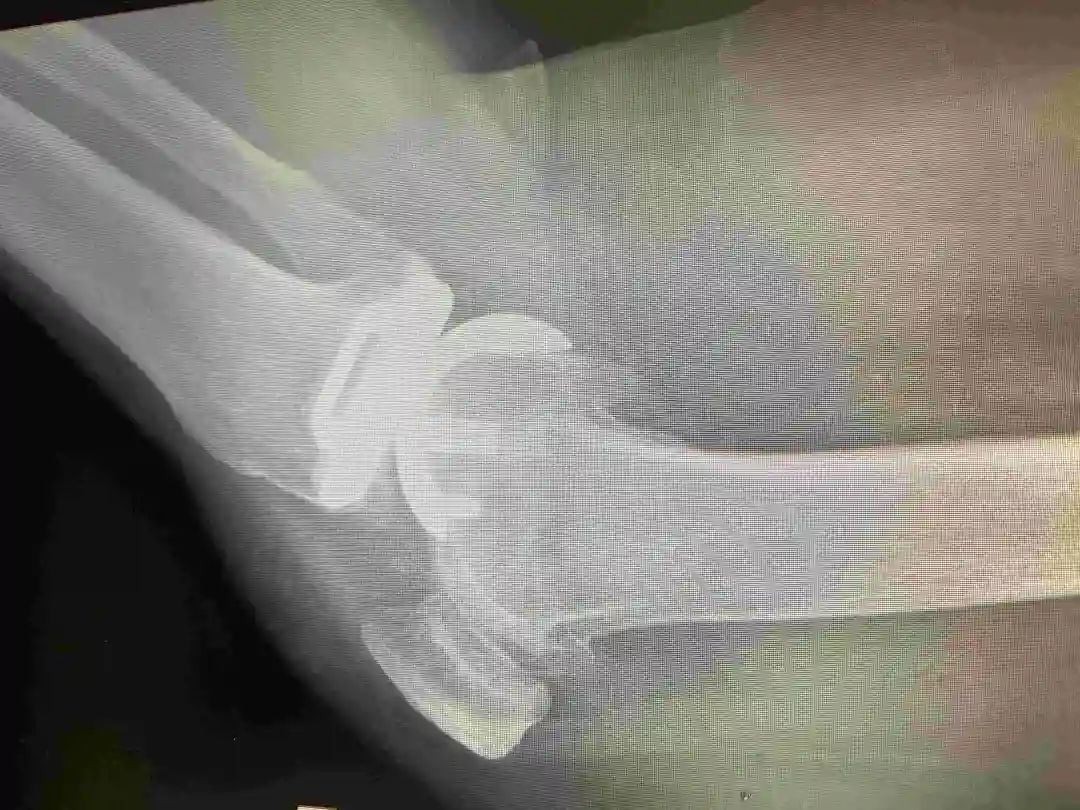

▲术前(上图)术后(下图)影像资料

后经人介绍,刘奶奶在我院经相关检查后,行左膝单髁关节置换术,手术非常顺利,术后恢复良好,左膝关节无疼痛,活动自如。近两月,患者右膝关节的旧疾疼痛加重,复查发现这又是右膝内翻畸形带来的“烦恼”。于是便在我院再行右膝单髁关节置换术。现术后双膝关节活动自如,行走无碍。困扰了刘奶奶20多年的“老毛病”至此终于告一段落!